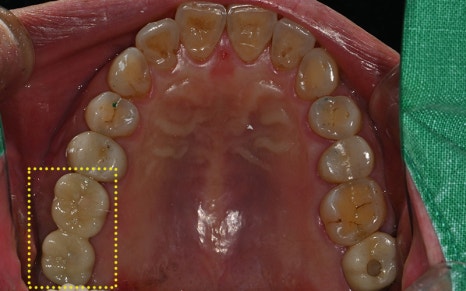

✅ 치료 완료 후 보철물까지 완성!

교합을 섬세하게 고려하여

정밀하게 보철작업까지

완료된 모습입니다!

이렇게 성공적인 임플란트 치료사례에 대해

소개해드렸는데요!

환자분께서도 결과에 매우 만족하셨답니다 :)